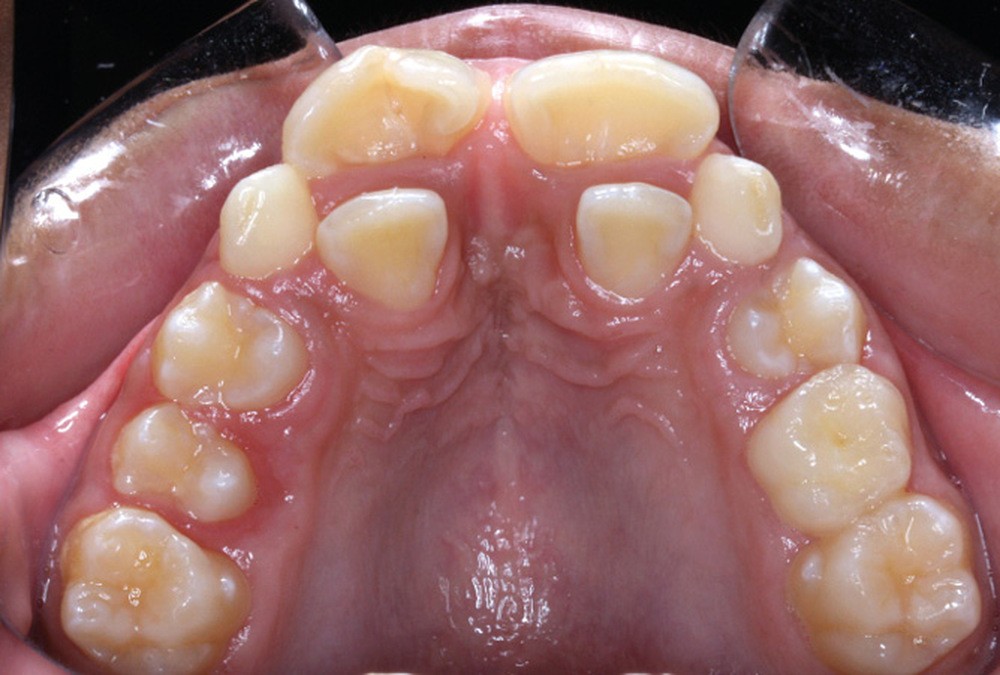

Antony, 11 ans se présente initialement pour une demande esthétique concernant ses deux incisives centrales qu’il trouve trop grosses (fig. 1a-c).

Le profil est convexe et associé à une inocclusion labiale au repos. Il s’agit d’une classe II squelettique sur un schéma facial normodivergent. Les rapports occlusaux sont de classe II bilatérale (complète au niveau molaire) avec des incisives inférieures vestibulo-versées. La 21 est géminée et la 11 vraisemblablement fusionnée avec un germe surnuméraire, sans altération de la formule dentaire. Du fait du diamètre mésiodistal fortement augmenté des incisives centrales, et du manque de place à l’arcade maxillaire qui en découle, les 12 et 22 sont en inversé d’occlusion en palato position. Les 53 et 63 sont persistantes sur l’arcade avec une inclusion en transposition incomplète de la 13, dont la cuspide se situe entre la racine de la 12 et celle de la 11 résorbée (fig. 1d-g).